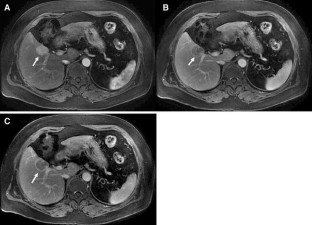

Hepatocellular Carcinoma in Budd-Chiari Syndrome: Enhancement Patterns at Dynamic Gadolinium-Enhanced T1-Weighted MR Imaging

The objective of this study was to analyze the enhancement patterns at dynamic gadolinium-enhanced T1-weighted MR imaging in patients of Hepatocellular Carcinoma (HCC) with associated Budd-Chiari syndrome (BCS). The MR imaging findings in 10 patients of HCC with associated BCS were compared to those of 32 other patients of HCC without BCS. During the arterial phase, significantly more lesions with BCS were hyperintense than lesions without BCS; during the equilibrium phase, significantly more lesions with BCS were slightly hyperintense or isointense than lesions without BCS (P < 0.05 for both). For HCC, contrast enhancement on MRI shows different enhancement patterns between patients of HCC with associated BCS and those without BCS.

Fig. 1